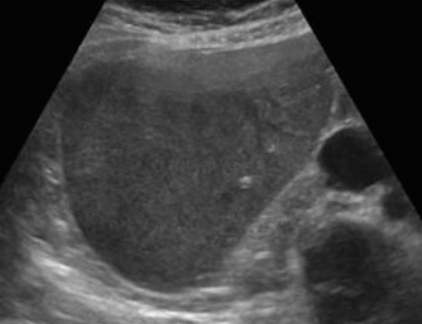

hepatocellular adenoma (간세포선종) US finding

- 원형의 저에코, 등에코, 고에코등의 종괴로 다양하다.

- 피막을 갖는다

- 크기가 8~14cm으로 크다

- 간전이암이나 간세포암과 정확히 구별이 어렵다.

- hypoechoic rim (띠가 혈관이다)

- usually solitary and heterogeneous